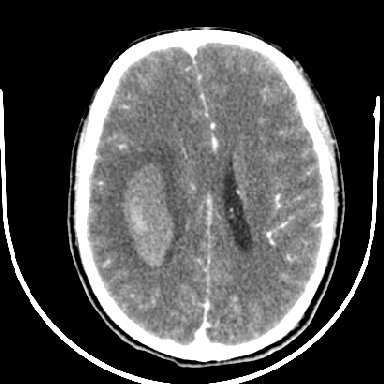

标题: CT6056:脑出血(血管畸形?) [打印本页]

标题: CT6056:脑出血(血管畸形?)

m 40突发头痛左侧偏瘫3小时

考虑高血压性脑出血,依据:

1是高血压性脑出血的好发部位,形态呈肾形,是高血压性脑出血的常见形状

2增强时占位效应加重了,考虑出血还没有停止

3病灶周围水肿不是太厉害,一般肿瘤出血水肿多非常明显

4病灶周围的‘软组织’影没有明显的强化

5至于脑血管畸形引起的出血,暂时没有看到明显的畸形血管影,也不太支持

支持右侧基底节脑出血

右侧基底节区脑出血.

支持右侧基底节区(主要为外囊区)原发性脑出血。

另附部分资料:“血液溢出血管外形成血肿,其内含有大量血红蛋白、血浆白蛋白,球蛋白,因这些蛋白对x线的吸收系数高于脑质,故ct呈现高密度阴影,ct值达40~90h,最初高密度灶呈非均匀一致性,中心密度更高,新鲜出血灶边缘不清。基底节区血肿多为“肾”型,内侧凹陷,外侧膨隆,因外侧裂阻力较小,故向外凸,其它部位血肿多呈尖圆形或不规则形”

术中抽出40ml陈旧血液,血肿底部似见一条索血管影